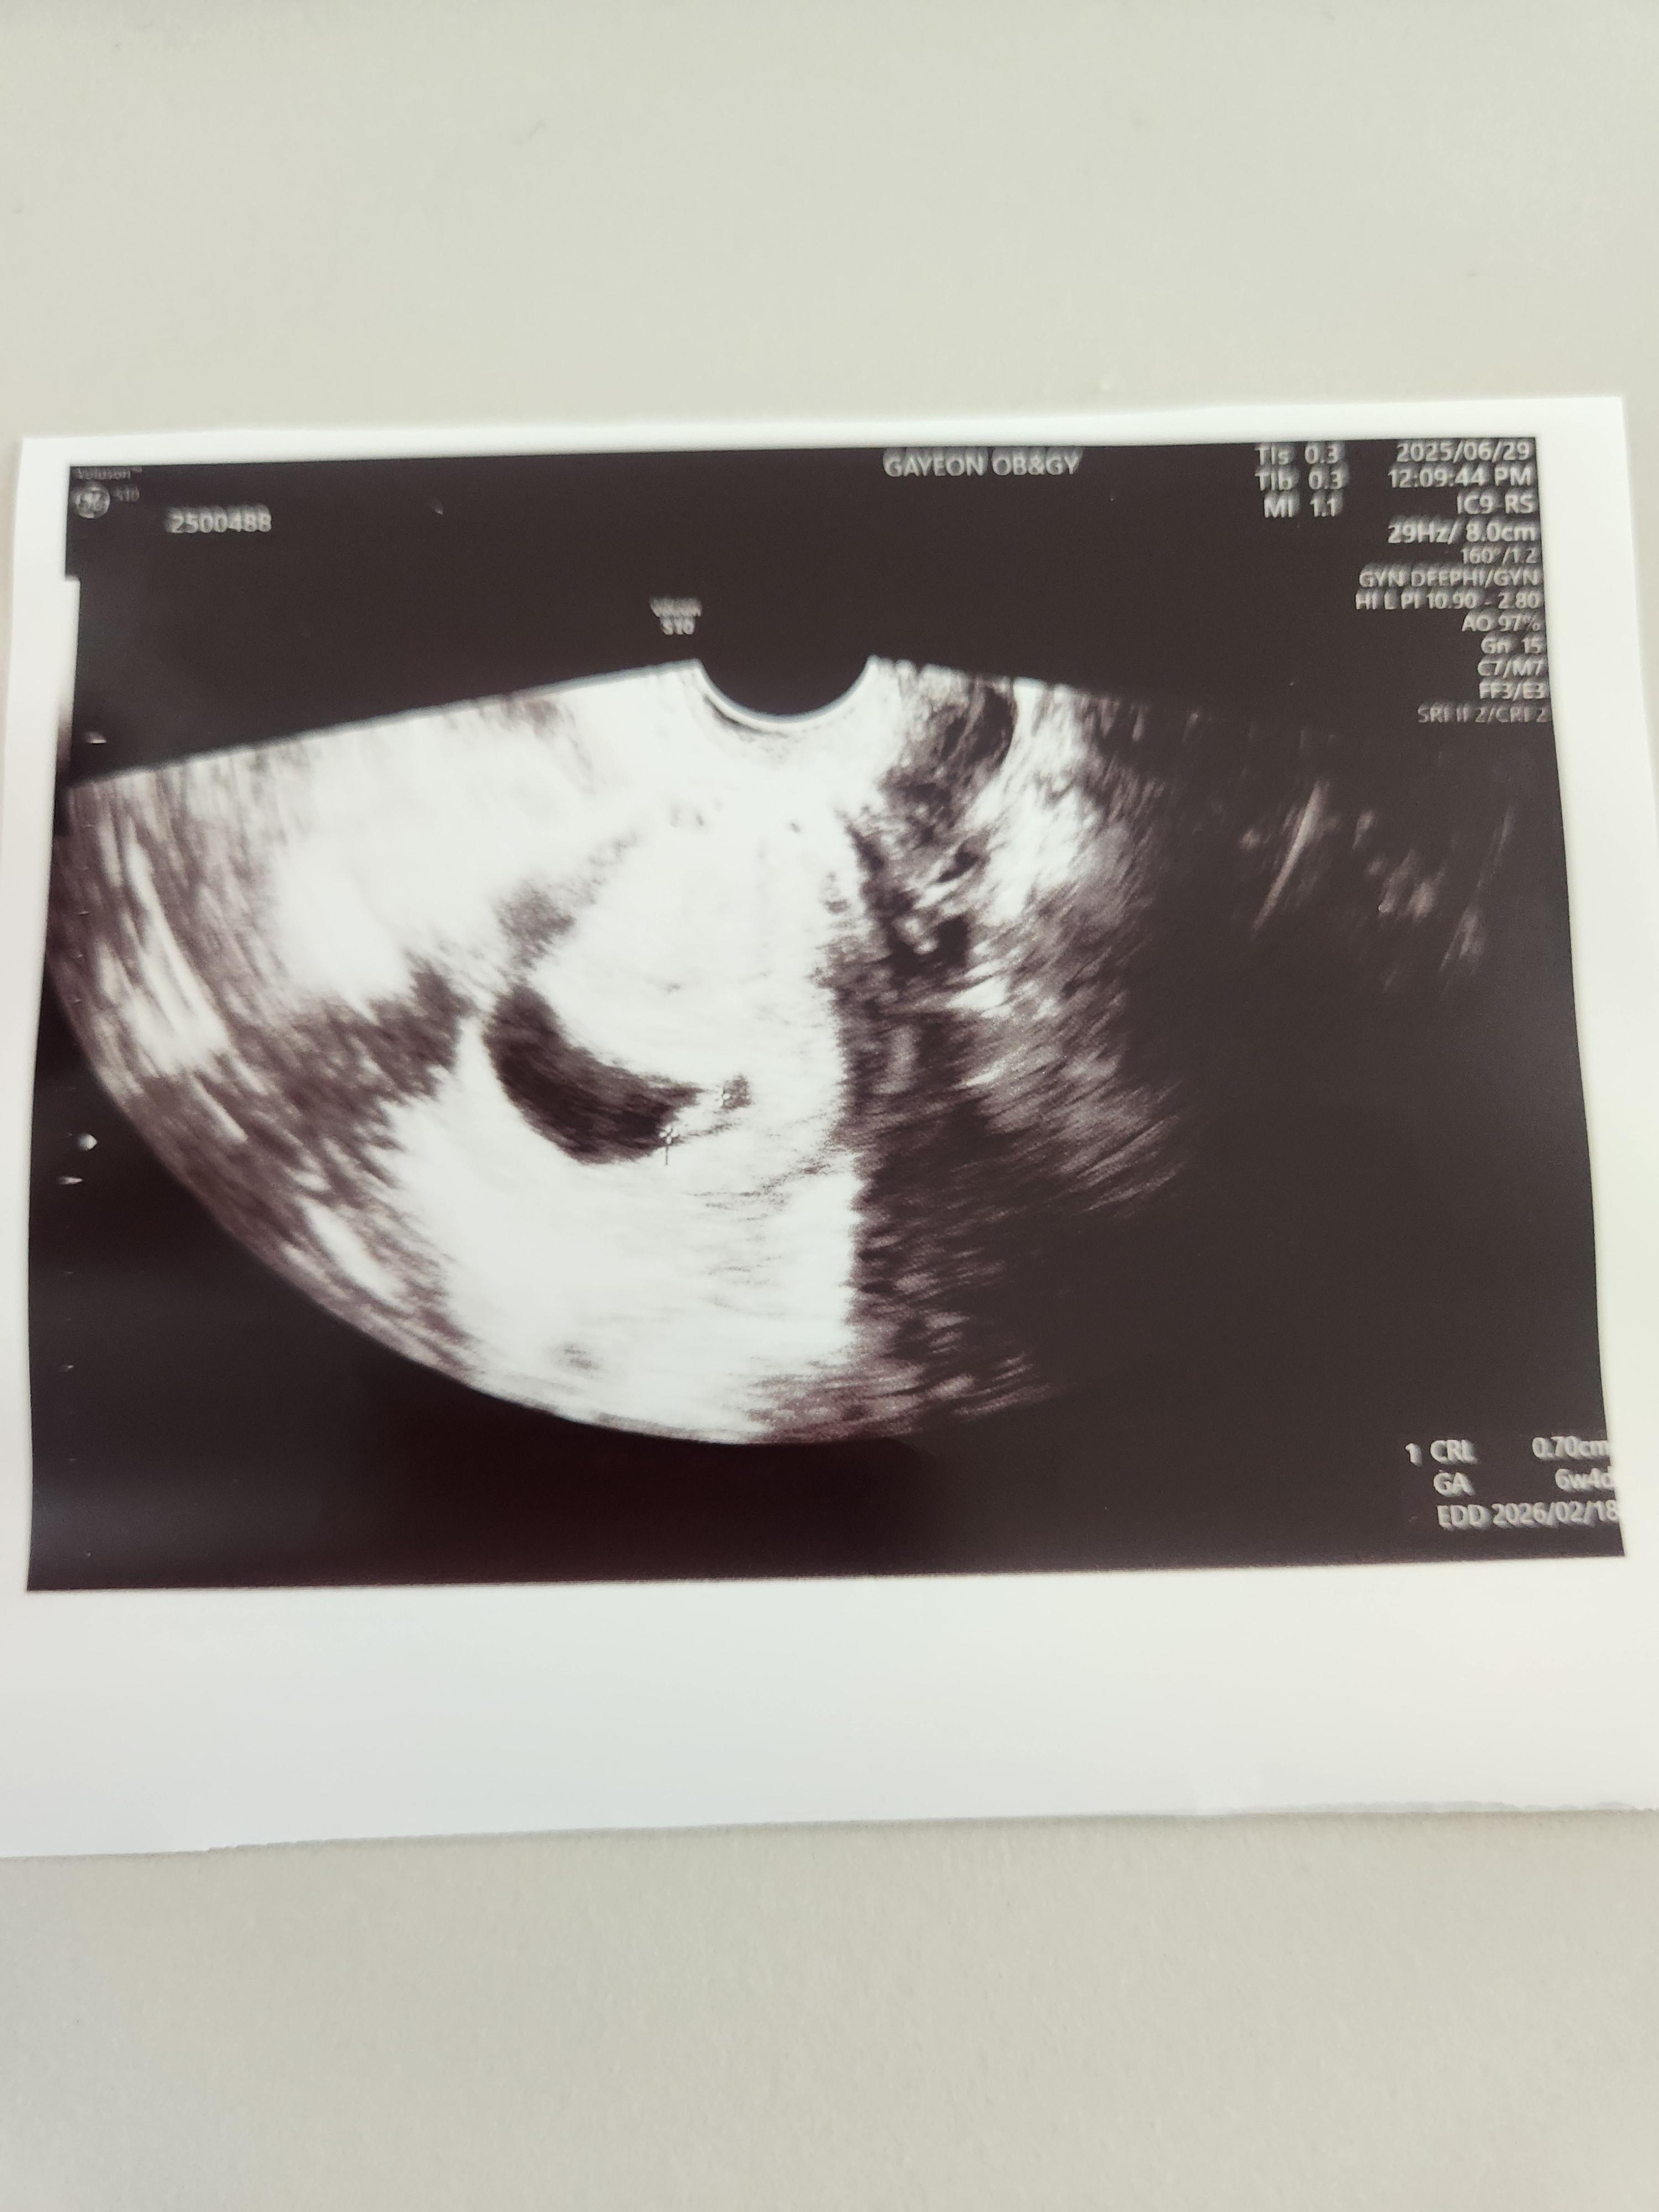

임신 6주 차(6주 4일 차) , 임신 초기 아기 심장소리를 초음파로 확인한 후기에 대해 알려드리겠습니다.

지금 아기 주수는 6주 차, 6주 4일 차이며, 저번에 초음파를 봤을 땐 아기집만 보였는데, 지금은 아기집도 조금 더 커졌으며 안에 배아가 보이기 시작했습니다.

의사 선생님께서 아기심장이 아주 잘 뛰고 있다고 해주셨습니다.

아기는 아주 건강하게 잘 있다고 하셔서 안심할 수 있었습니다.